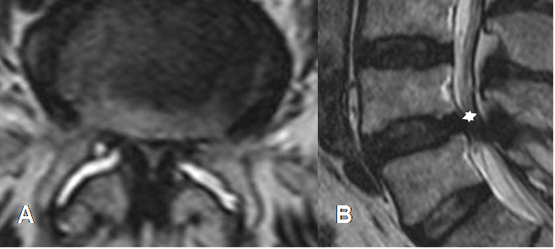

Fig 63. Canal estrecho.

A: RM axial y B: RM sagital en T2. Canal estrecho mixto, con disminución del diámetro AP.